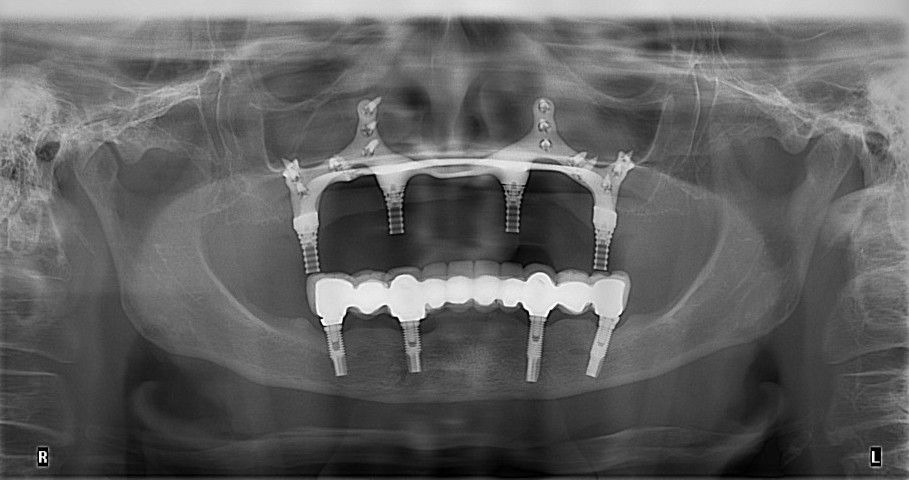

I have experience in oral surgery procedures such as: simple extractions, extraction of impacted teeth and third molars, biopsies, frenectomies, dental implants, zygomatic implants, juxta-osseous implants, and guided bone and tissue regeneration.

- Implantes cigomáticos